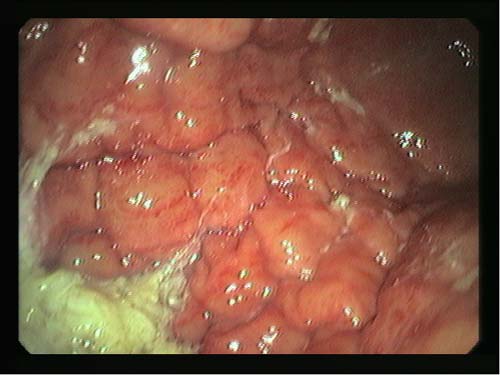

Linitis gástrica plástica.